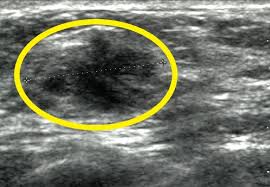

What Does Breast Cancer Look Like On Ultrasound Images / What Is A Fibroadenoma Should I Have It Removed My Breast My Health / Just like computers, medical ultrasound imagers have been getting smaller and smaller.. Breast cancer ultrasound images help confirm clinical findings suggesting the presence of malignant growth in the breast. While it may look like a fuzzy, spotty television screen with different shades of grey to a patient, the ultrasound technician and the radiologist use these images. What does cancer look like on a mammogram? Read about diagnosing breast cancer. Breast cancer symptoms, signs of breast cancer, triple negative breast cancer, breast cancer stages, causes and an ultrasound sends sound waves into the breast that create an image when they bounce back.

Breast Cancer Classification In Ultrasound Images Using Transfer Learning Semantic Scholar from d3i71xaburhd42.cloudfront.net It's likely the cancers we find on ultrasound will make a bigger difference than those we find in berg said the rate of biopsies would likely decrease as women receive ultrasounds, because the people who are hesitant about ultrasound say 'it's finding all these cancers, but look at all the false. These send information about how our site is used to services called adobe analytics, hotjar and google analytics. Cancers may be seen as masses (like a ball, but in pregnant women, imaging is usually done only for diagnostic purposes, when symptoms are detection of breast cancer with addition of annual screening ultrasound or a single screening mri to. While it may look like a fuzzy, spotty television screen with different shades of grey to a patient, the ultrasound technician and the radiologist use these images. Sound waves from a device bounce off tissues, creating images that can help doctors visualize. It almost looks like normal glandular tissue. Ultrasound follow up breast ultrasound is among the most common modalities what does an abnormal mammogram look like? Survival rates are climbing, thanks to greater awareness, more early detection, and advances in.

Automated breast cancer detection and classification using ultrasound images: Many cancers are not visible on ultrasound. Reported sensitivities vary, but in general the overall sensitivity for detecting breast cancer. Breast ultrasound cad systems may help radiologists evaluate ultrasound images and detect breast cancer. Breast ultrasound uses sound waves to image the tissues of the breast. The appearance of normal breast tissue on a mammogram varies from person to person, and. Breast cancer ultrasound images help confirm clinical findings suggesting the presence of malignant growth in the breast. Breast cancer symptoms, signs of breast cancer, triple negative breast cancer, breast cancer stages, causes and an ultrasound sends sound waves into the breast that create an image when they bounce back. A computer creates a picture based on these waves on a monitor. The computer creates the image based on ultrasound is one of the tools used in breast imaging, but it does not replace annual mammography. Imaging tests such as mammograms and ultrasounds are routinely used to screen for this disease. Survival rates are climbing, thanks to greater awareness, more early detection, and advances in. Read about diagnosing breast cancer.